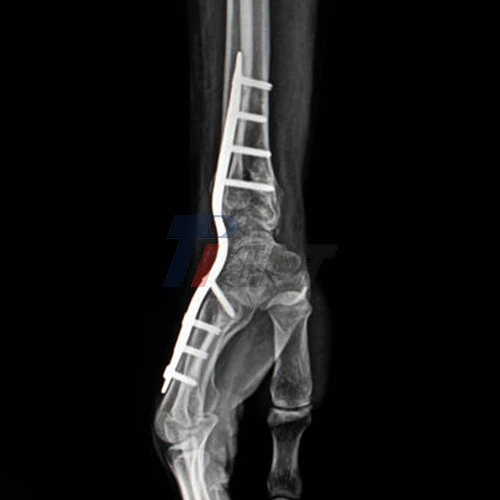

A titanium plate is surgically implanted and fastened to the damaged bone with tiny screws when it is used to treat a wrist fracture. Open reduction and internal fixation (ORIF) is a technique that enables surgeons to precisely realign shattered bones and keep them in place while they recover.

Stable Fixation: Titanium plates provide a level of stability that is crucial for proper bone healing. By keeping the fractured bones firmly in place, these plates create an optimal environment for new bone formation. This stability minimizes micro-movements that could otherwise disrupt the healing process, allowing for faster and more efficient bone union.

Customization and Precision: Advanced manufacturing techniques allow for the creation of titanium plates that are precisely tailored to the patient's anatomy and the specific fracture pattern. This customization ensures optimal fit and alignment, which can contribute to faster healing and better functional outcomes.